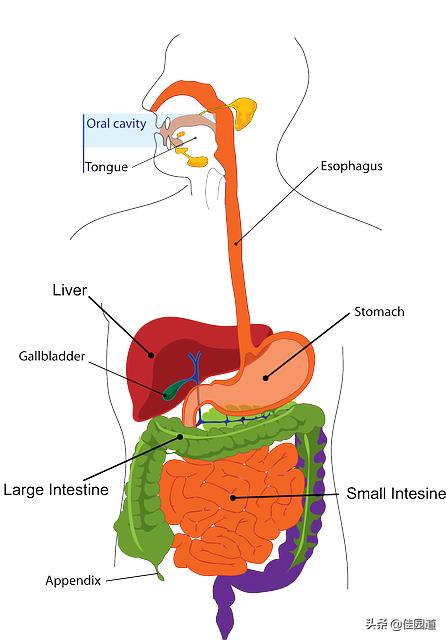

いわゆる胃がんは、間違いなく私たちの体内に発生する。胃部悪性腫瘍のしかし、胃の悪性腫瘍は胃癌とは異なることに注意すること。つまり、胃に発生する悪性腫瘍は、おなじみの胃がんに加えて胃リンパ腫、胃間葉系腫瘍など他の悪性腫瘍もある。しかし、胃がんは胃の悪性腫瘍の中で最大の数を占めている。95%以上さらにわが国は有病率が高い.わが国ではここ数年、胃がんの罹患率は低下しているが、胃がんの罹患率は依然として高い。胃がんによる死亡者数は特に激減していない。男女ともに胃癌の発生率は悪性腫瘍の中で2番目と5番目に高く、死亡率は3番目と2番目に高い。55~70歳が有病率の高い年齢層である。。

ご存知のように、胃は私たちの体の中にあり、消化器系の重要な器官である。通常、胃は4つの部分に分けられ、心窩部に近い部分は「胃」と呼ばれる。ふんもん心窩部平面の上方、左上に広がっている部分は胃底と呼ばれ、眼底から角切欠きに至る胃の中央部分はコーポラス最終胃の下縁と幽門の間の部分は幽門部と呼ばれ、臨床的には幽門部とも呼ばれる。胃窦。

胃がんの好発部位は、肛門、噴門、胃体部である。対応する胃壁粘膜層の上皮細胞いくつかの悪性腫瘍の後に起こる胃の癌性変化は胃癌と呼ばれる。